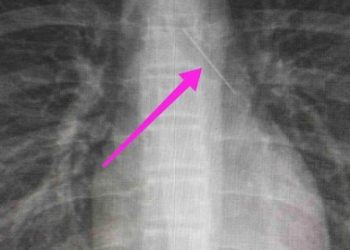

Θεσσαλονίκη: Ανήλικη κατάπιε καρφίτσα – Είχε σταθεί στον δεξιό βρόγχο

Με επιτυχία ολοκληρώθηκε η προσπάθεια ιατρικής ομάδας του Γενικού Νοσοκομείου Θεσσαλονίκης «Ιπποκράτειο» για την αφαίρεση καρφίτσας από τον δεξιό πνεύμονα ...